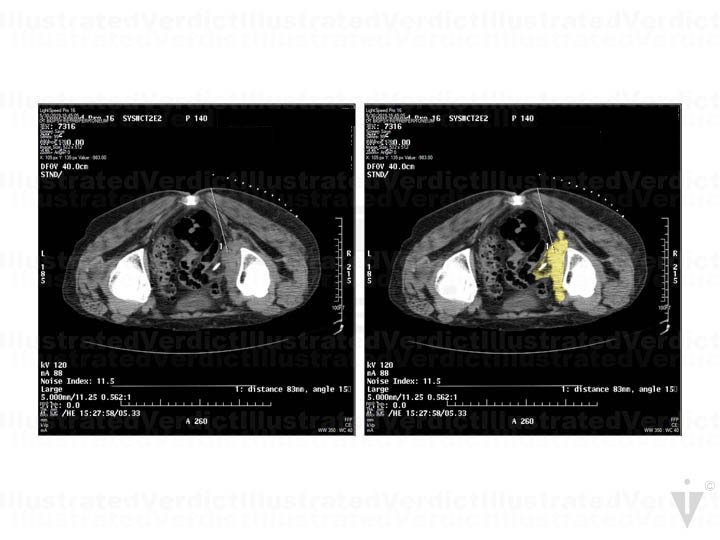

A 78-year-old woman with a history of infiltrating endometriosis presented with persistent, chronic pelvic, back, and flank pain. An MRI revealed a right-sided pelvic endometrioma mass, which encapsulated the right ureter and involved her pelvic nerves. She had a stent placed in the right ureter, and unfortunately, the pain increased. She underwent a CT-guided IRE as treatment. Post treatment, she felt pain in her right foot extending up her calf, and she experienced limited feeling in her right toes, foot, or ankle. A month after the procedure, her right pelvic, back, and flank pain had resolved, but she continued to have right leg paresthesia (pins and needles with numbing sensation). Unfortunately, nerve damage was a risk of the procedure. The jury found in favor of the defense.